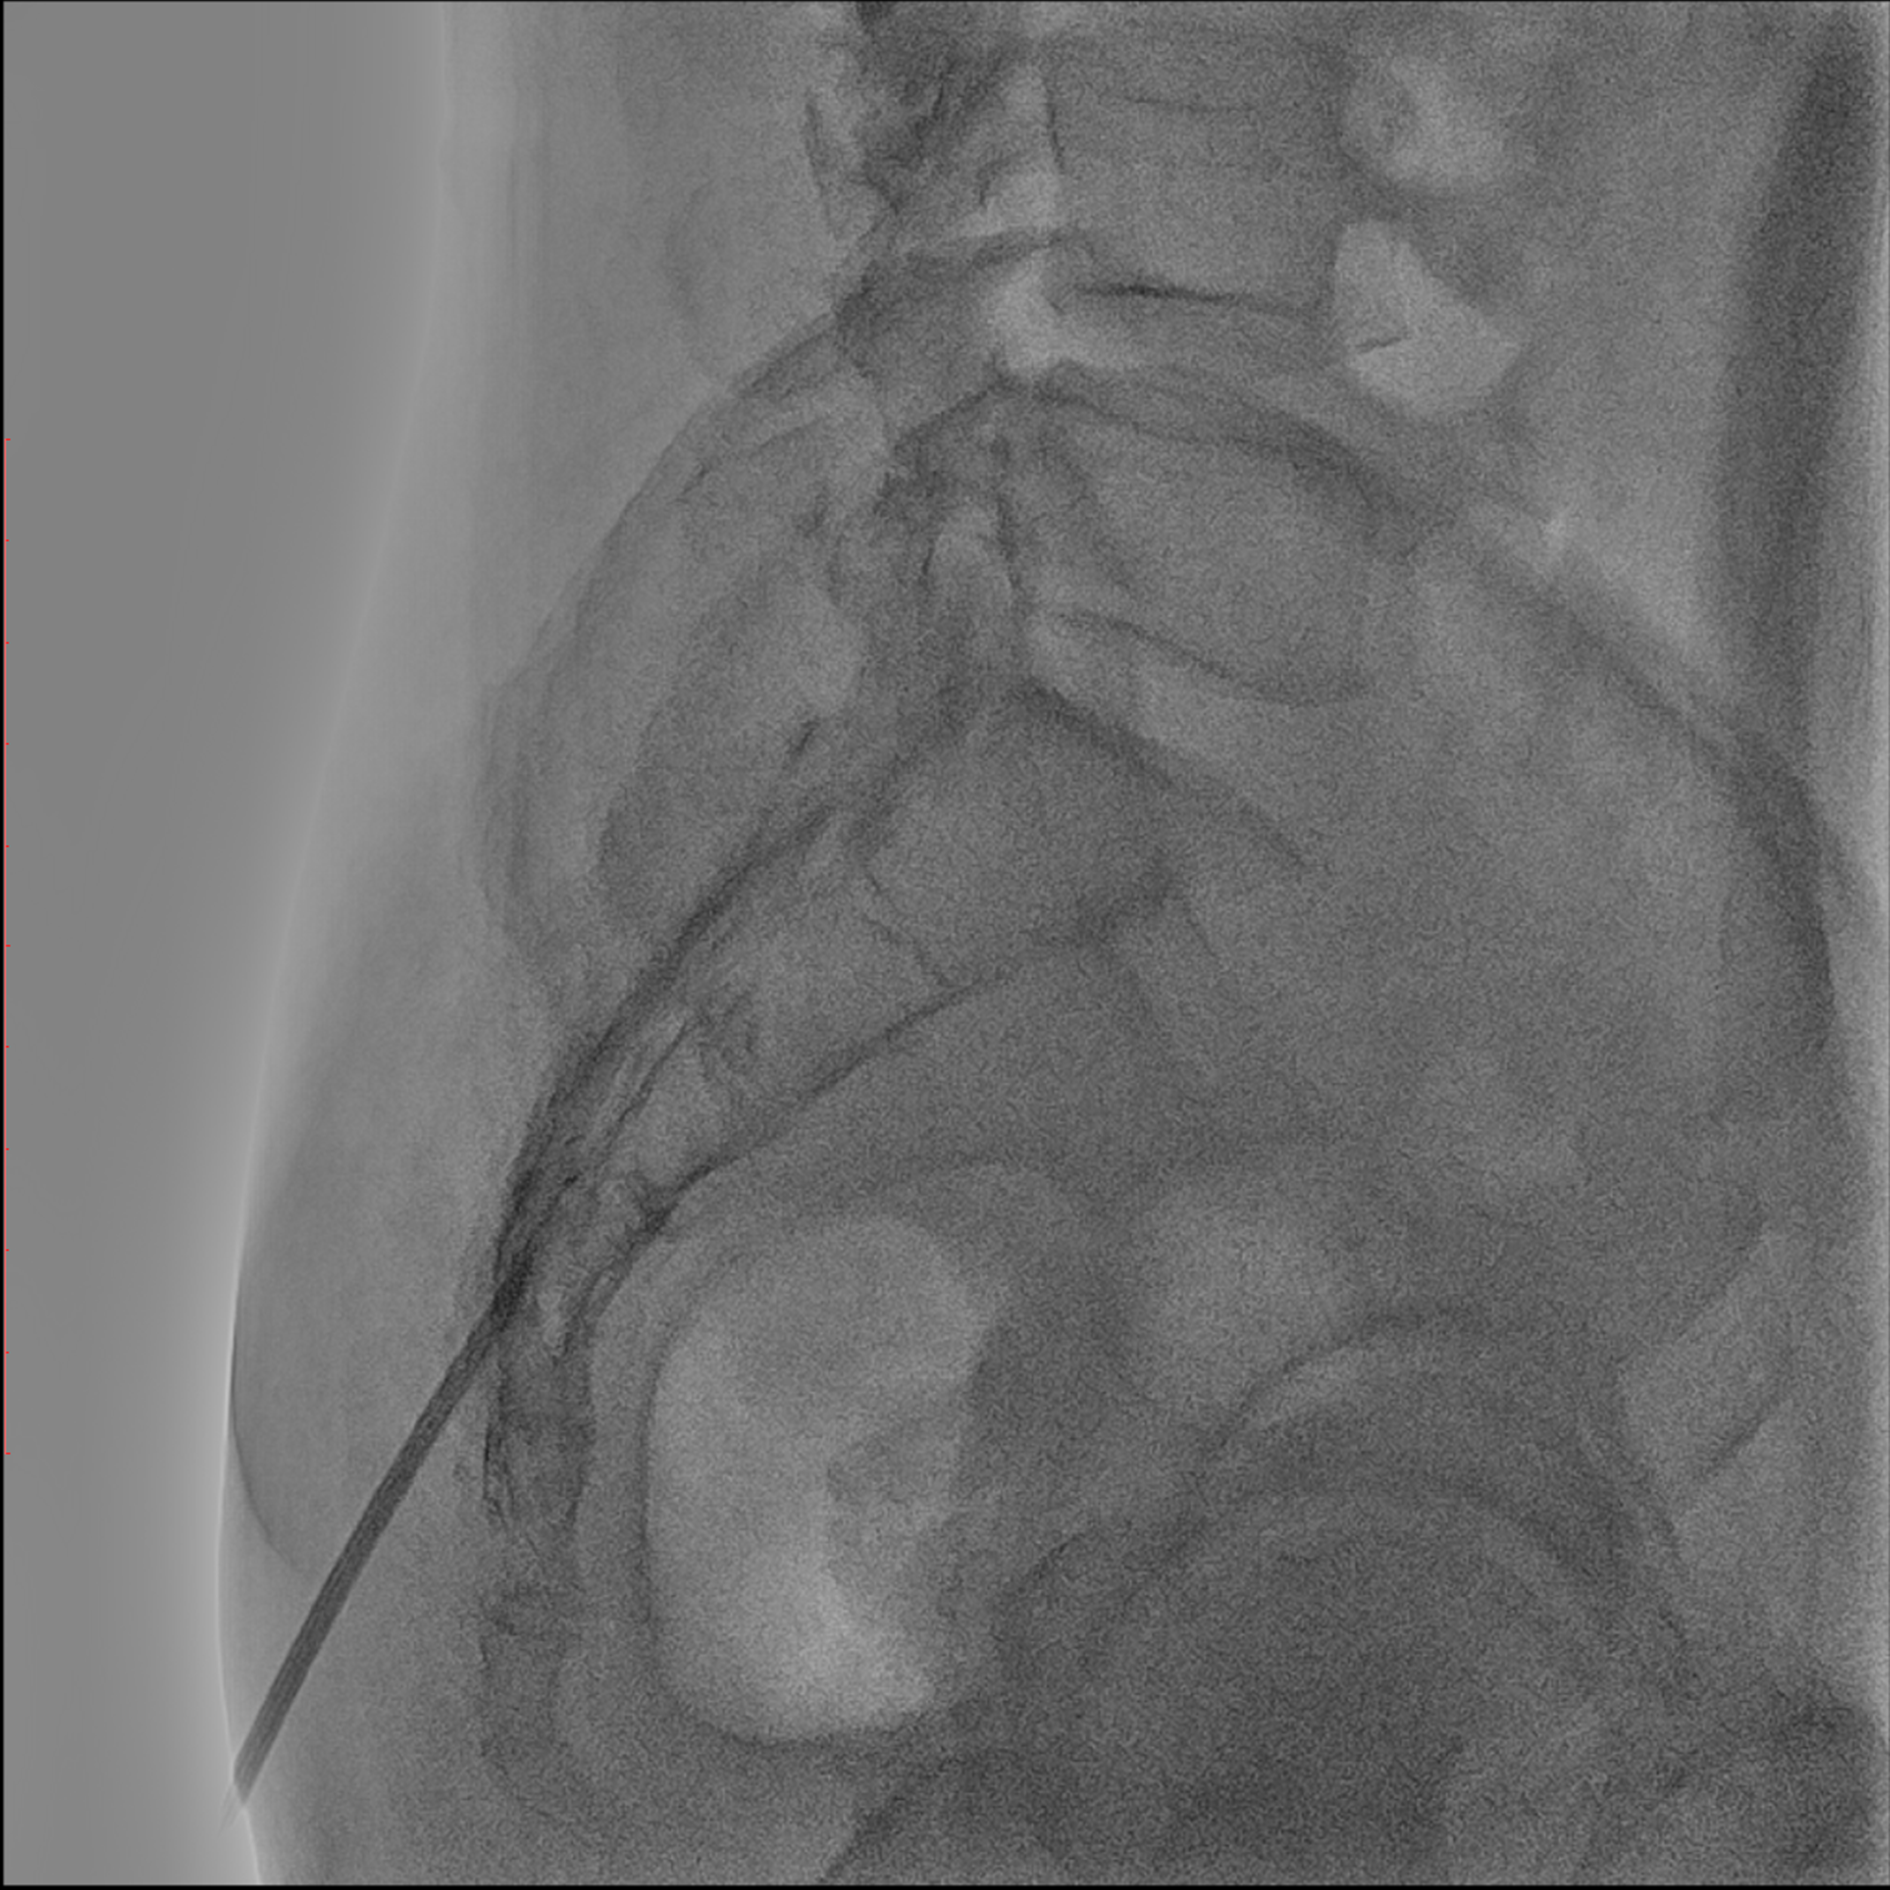

경막외 유착박리술, Epidural Neuroplasty